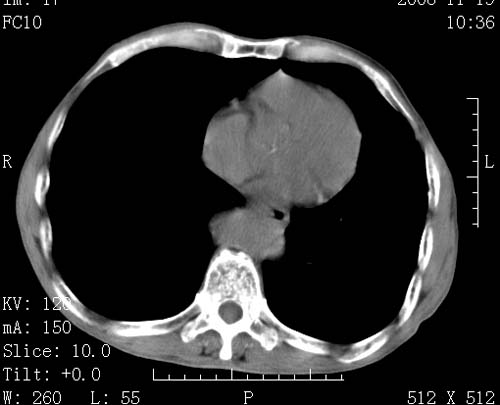

标题: CT16691:m 67 胃镜确诊食管下段及贲门癌 [打印本页]

标题: CT16691:m 67 胃镜确诊食管下段及贲门癌

术前查体,双肺部结节是转移?结核?请点评

1)符合食管癌表现。2)两肺及纵隔淋巴结多发性转移瘤。3)左肺上叶舌段及两肺下叶炎症感染。

食管癌伴双肺转移,评述:肺部毛细血管网丰富,全身血液均快速流经肺部,癌细胞容易过滤定植,形成转移瘤,影象特点为以毛细血管末梢为中心的结节灶,边缘光滑锐利,少见有中心空洞着,不同来源的转移瘤可有各自特点,如甲状腺癌为双肺弥漫性微结节,本例有原发灶,双肺影象灶典型,左肺舌段条带状网格样伴胸膜天幕征,可视为癌性淋巴管炎。